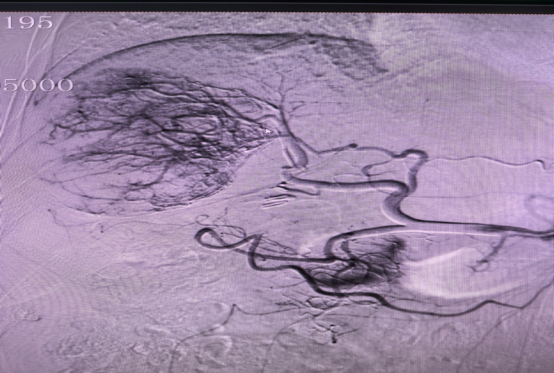

通过DSA造影找出显影的肿瘤供血动脉

微导管超选找到肿瘤供养血管,透视下缓慢注入碘油化疗栓塞乳剂及栓塞微球栓塞肿瘤责任血管

术后显示肿瘤供血动脉减少、消失,瘤体内碘油乳剂沉积良好